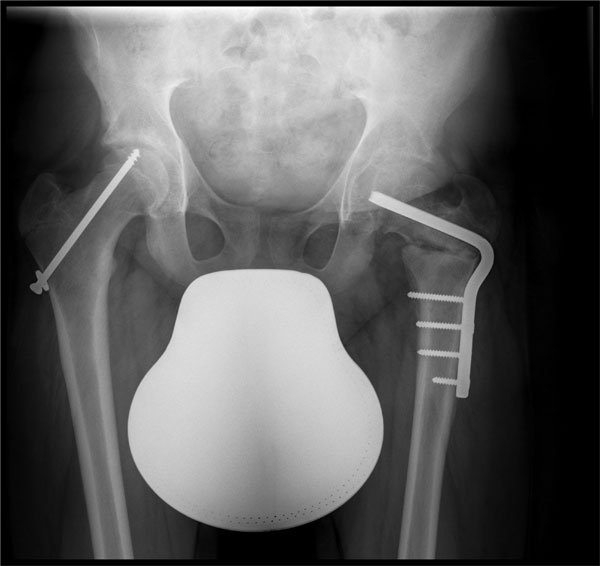

Prophylaktische Verschraubung gesunde

Seite und Spickung abgerutschte Seite

Ziel ist es, ein weiteres Abrutschen des Hüftkopfes zu verhindern. Der abgerutschte Hüftkopf wird bei der Operation fixiert, z.B. durch Spickung mit Drähten. Da die Erkrankung in vielen Fällen beidseitig auftritt, werden beide Hüftgelenke operativ versorgt. Bei einem schweren Abrutsch ist es häufig notwendig, weitere operative Maßnahmen am Hüftgelenk durchzuführen.